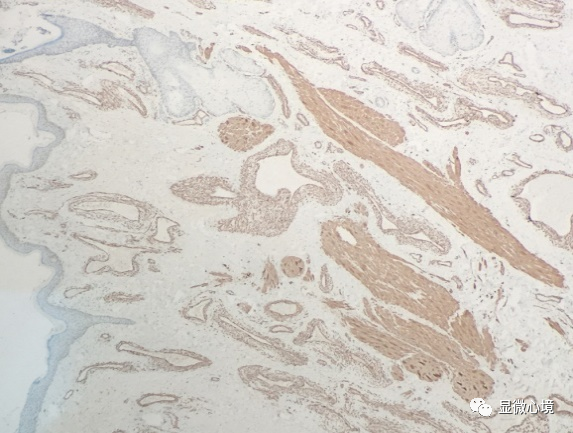

1免疫组化染色结果显示,畸形扩张血管内皮细胞呈CD34阳性表达,有助于清晰显示管腔分布范围及扩张程度

2  免疫组化染色结果显示,畸形血管壁呈SMA阳性表达,有助于显示管壁厚度及管腔轮廓,其中内对照竖毛肌呈胞浆强阳性表达